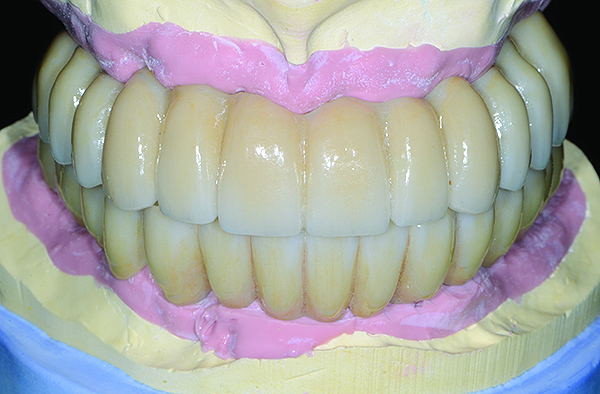

Fig 12. Extraoral frontal view of the completed maxillary and mandibular articulated zirconia restorations on master casts.

Figure 12